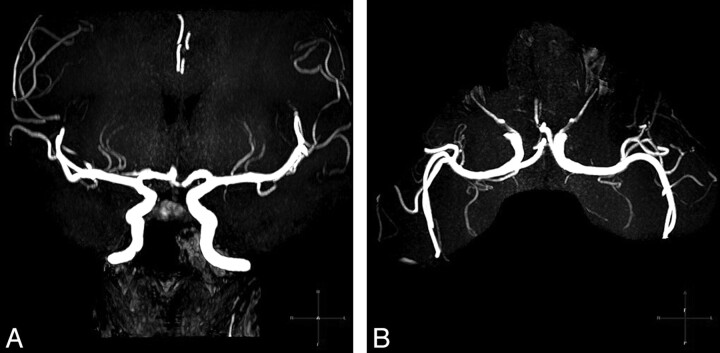

Fig 2.

3T 3D-TOF-MRA images of the LSAs of a patient with hypertension (a 39-year-old woman, BP = 154/100 mm Hg). Coronal MIP with a slab thickness of 20 mm (A) and axial 20-mm MIP (B) clearly show the LSAs branching from the MCA. The total number of the LSA stems counted from both sides is 4.